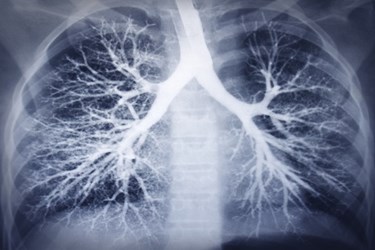

The Manchester Institute has expertise in the genetics of non-small cell lung cancer (NSCLC). The scientists intend to focus on the RET gene as it plays a role in thyroid cancer, non-small cell lung adenocarcinomas, and other cancers that originate in the airways. Investigators hope to find novel compounds to target the RET gene. Ian Miscampbell, managing partner of Sixth Element Capital, said they would seek industry partners for further development if initial studies find effective treatments.